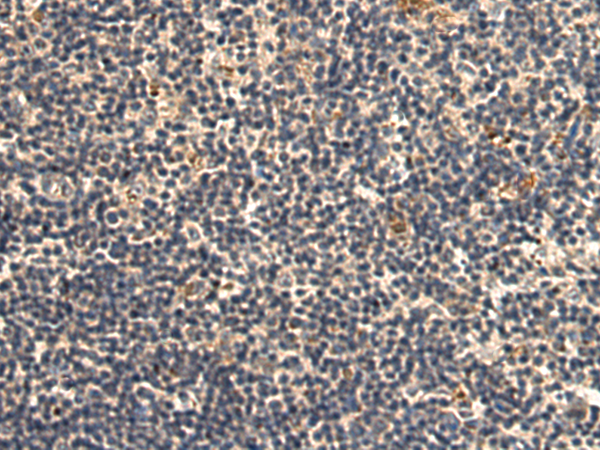

分类: 科研抗体货号: P07450别名: MIC-A; PERB11.1应用: WB,IHC反应种属: Human